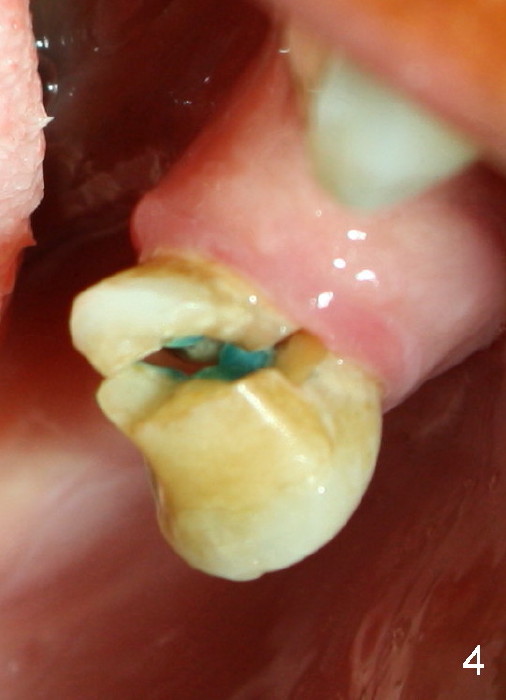

A 57-year-old lady has a lower partial. One of the abutments fractures (Fig.4). The apex is close to the presumably mental loop (Fig.3*; red dashed line: upper border of the inferior alveolar canal).